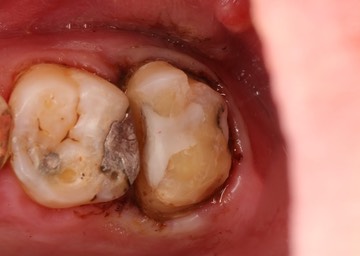

Kyle Chock #2 prep